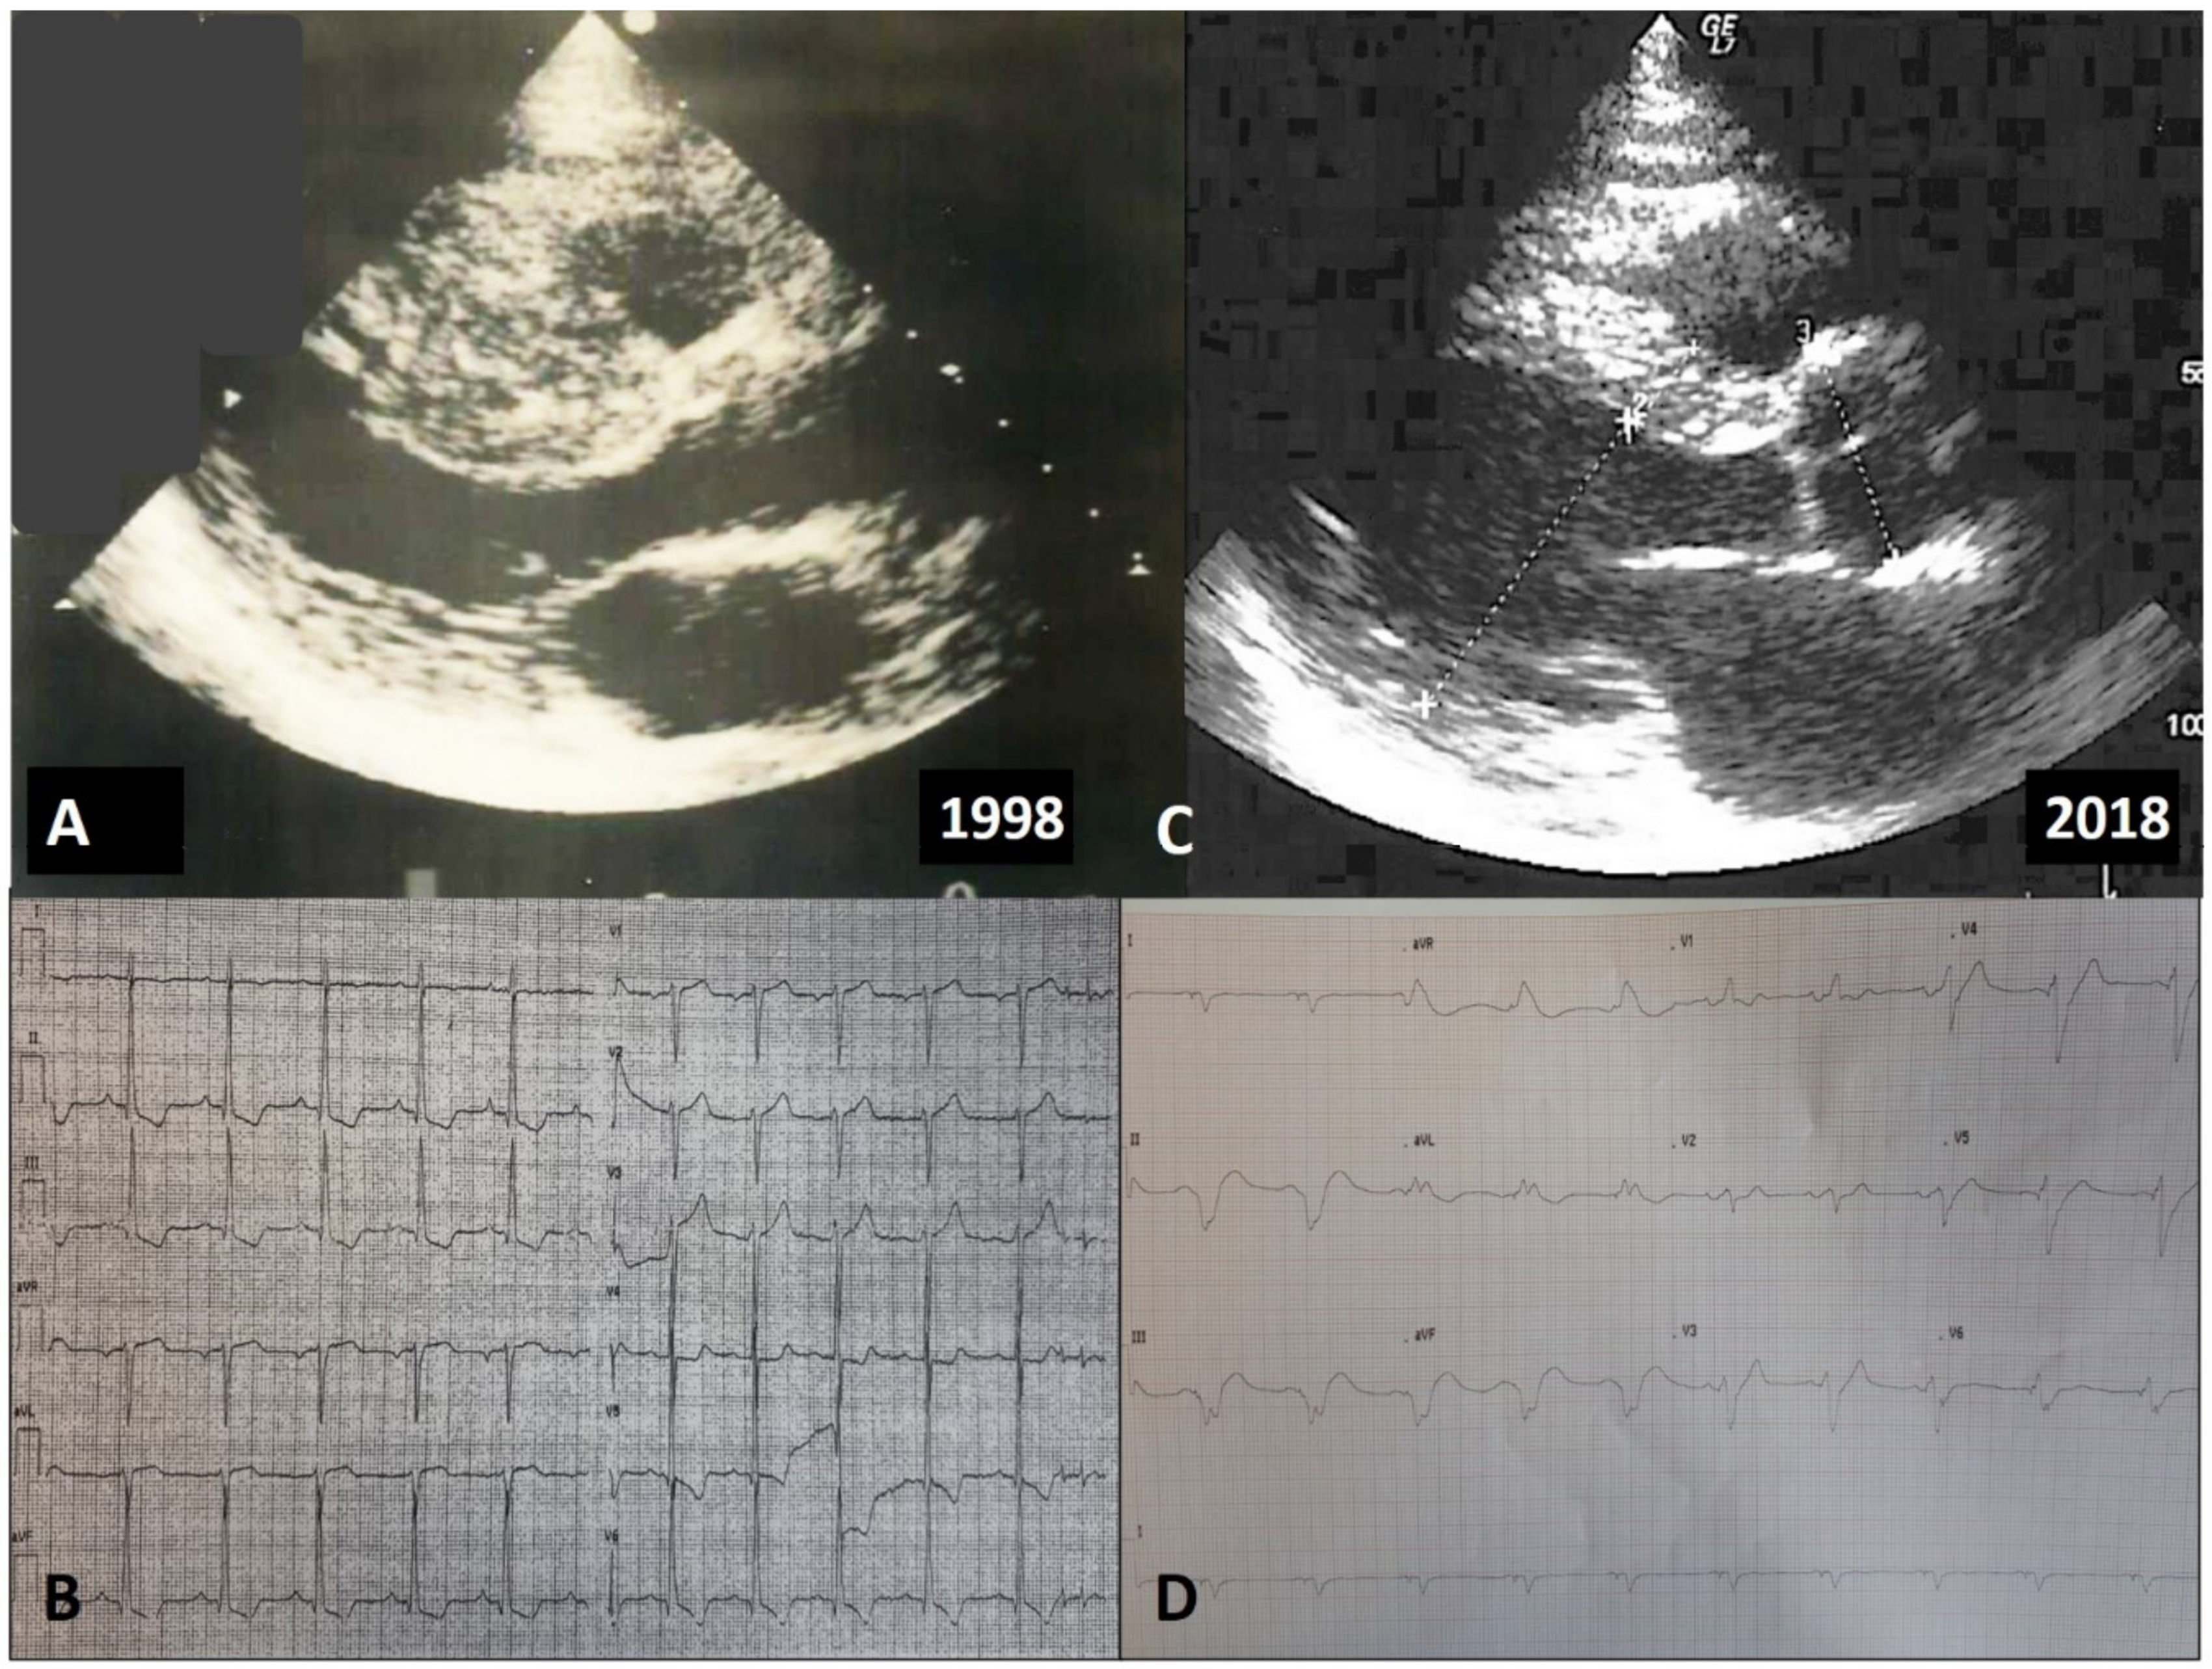

- Pennacchini, E.; Musumeci, M.B.; Conte, M.R.; Stöllberger, C.; Formisano, F.; Bongioanni, S.; Francia, P.; Volpe, M.; Autore, C. Electrocardiographic evolution in patients with hypertrophic cardiomyopathy who develop a left ventricular apical aneurysm. J. Electrocardiol. 2015, 48, 818–825. [Google Scholar] [CrossRef] [PubMed]